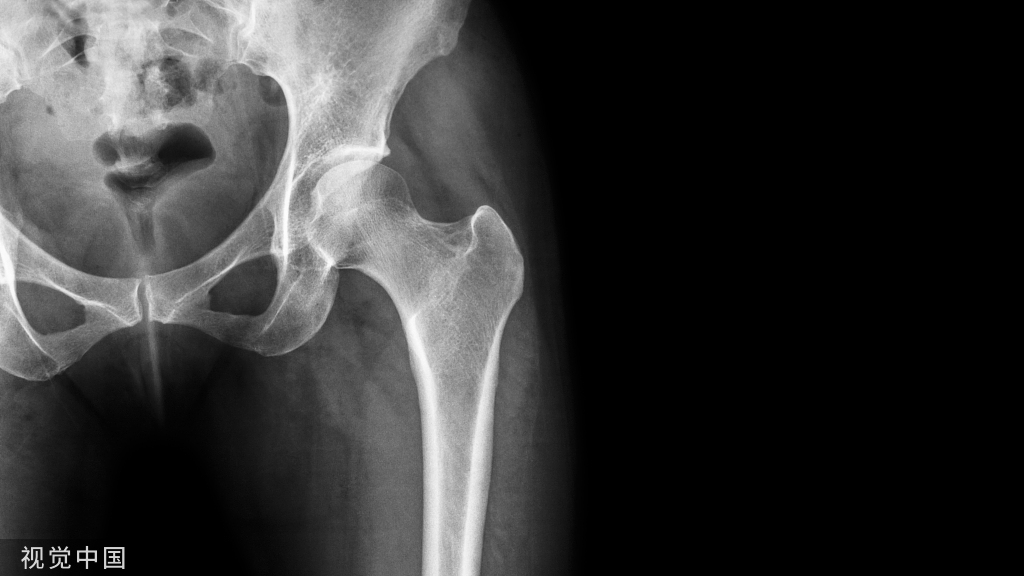

股骨交锁髓内钉

股骨钉适应症:

1、股骨粗隆下2cm距膝关节9cm以上的各种类型骨折。

2、股骨干中段陈旧性骨折。

3、钢板内固定失败者。

股骨交锁钉的特点:

1、固定骨折的力臂比钢板长,作用力均匀分散在整个骨干的中轴上,不易发生折弯变形。

2、锁钉使骨干从上到下形成一体,防止缩短和旋转,对骨折的固定达到最大的稳定性。

股骨转子间骨折内固定选择:

Evans 分型

I型为顺转子间型(分四个亚型)。

‖型为反转子间型,由于内收肌的作用,骨折远端向内侧移位。

Evans分型定义了稳定骨折与不稳定骨折。